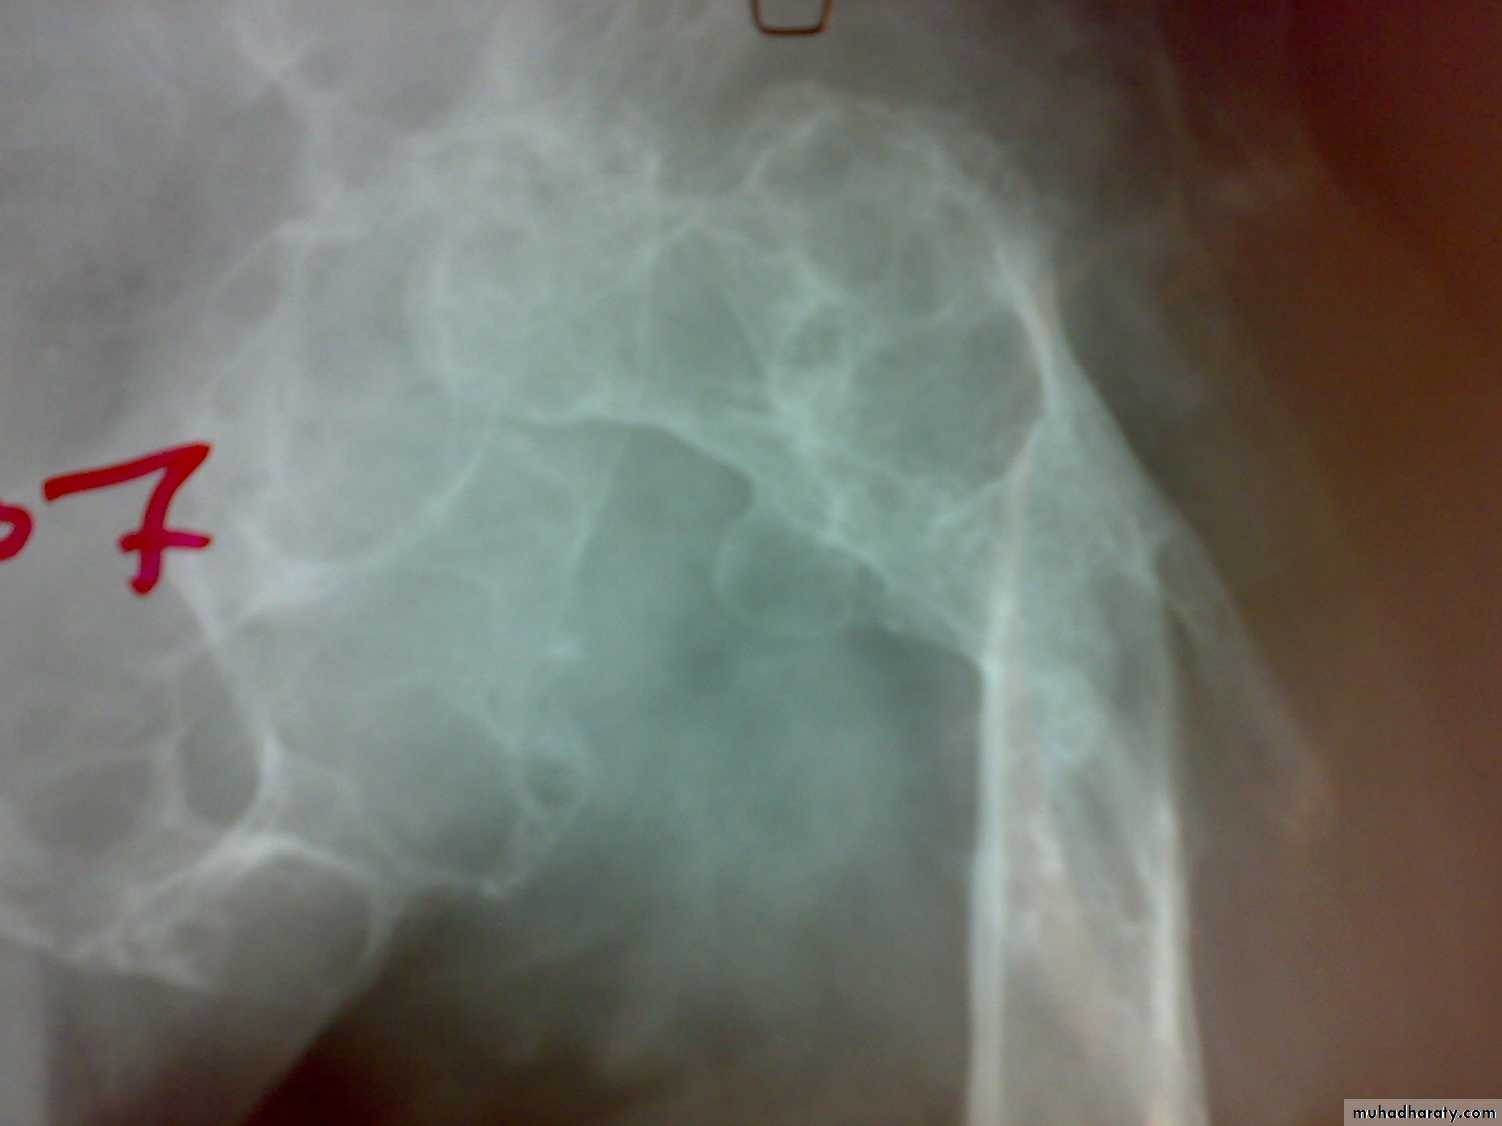

Hydatid disease of bone

Hydatid disease affect bone in 1-2%.

The cyst slowly enlarged in bone with little respect to cortical or epiphyeseal boundaries.

The bones most commonly affected are the vertebrae, pelvis, femur, scapula and ribs.

Patiens may complain of pain and swelling or pathological fractures.

It most differentiated from benign and malignant bone tumors.

Treatment by radical resection if possible with prolonged courses of albendazole.